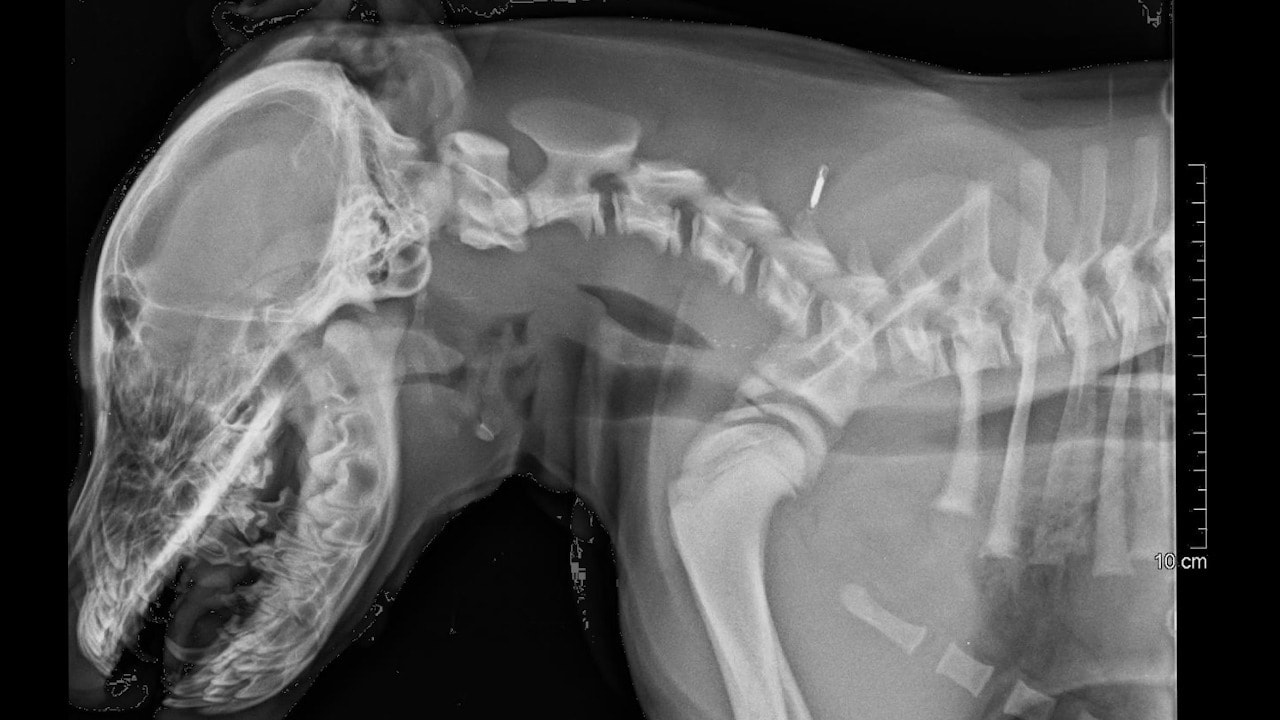

Obduktionen visar dock att hundvalpens skador har skett genom upprepat trubbigt våld med avsevärd kraft mot huvudet, samt mot bröstkorg och buk med akuta blödningar som följd.